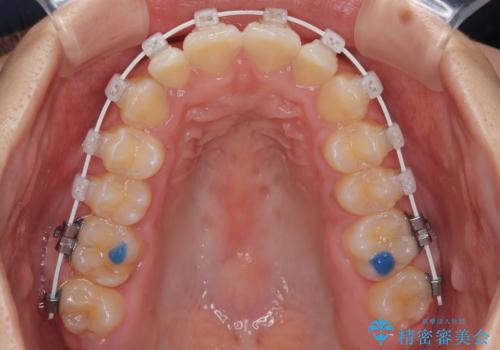

- 矯正装置

- 審美装置

・目立ちにくい審美装置による矯正

・治療期間をできるだけ短縮するために、綿密な装置管理と協力体制を構築